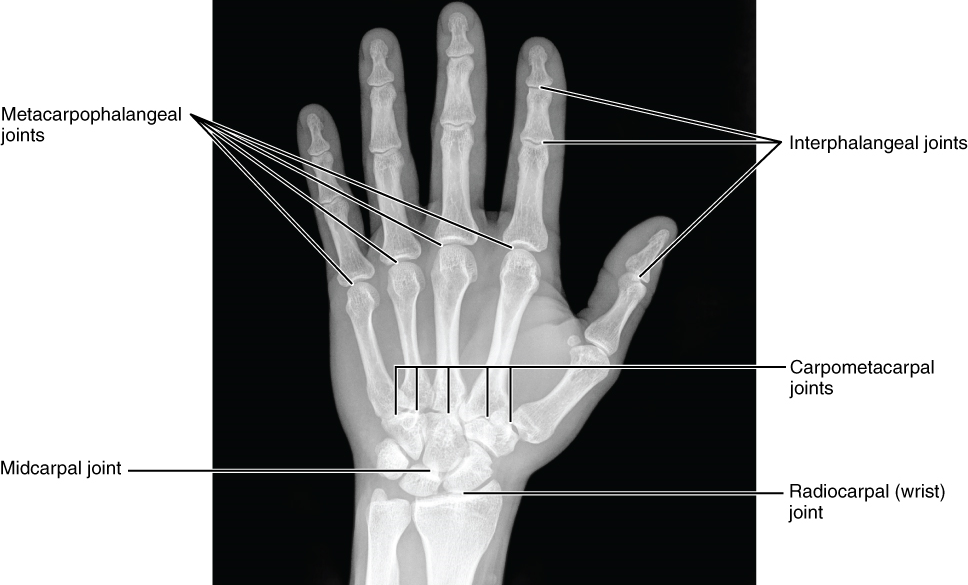

Radius: The radius runs parallel to the ulna, on the lateral (thumb) side of the forearm (Figure 33). The head of the radius is a disc-shaped structure that forms the proximal end. The distal end of the radius has a smooth surface for articulation with two carpal bones to form the radiocarpal joint or wrist joint (Figure 34 & 35).

Carpal Bones: The wrist and base of the hand are formed by a series of eight small carpal bones (Figure 34). The carpal bones are arranged in two rows, forming a proximal row of four carpal bones and a distal row of four carpal bones.

Figure 35. Bones of the Hand. This radiograph shows the position of the bones within the hand. Note the carpal bones that form the base of the hand. (credit: modification of work by Trace Meek)

The carpal bones form the base of the hand. This can be seen in the radiograph (X-ray image) of the hand that shows the relationships of the hand bones to the skin creases of the hand (Figure35).

Metacarpal Bones: The palm of the hand contains five elongated metacarpal bones. These bones lie between the carpal bones of the wrist and the bones of the fingers and thumb (Figure 34). The proximal end of each metacarpal bone articulates with one of the distal carpal bones. Each of these articulations is a carpometacarpal joint (Figure 35). The expanded distal end of each metacarpal bone articulates at the metacarpophalangeal joint with the proximal phalanx bone of the thumb or one of the fingers. The distal end also forms the knuckles of the hand, at the base of the fingers. The metacarpal bones are numbered 1–5, beginning at the thumb.

Phalanx Bones: The fingers and thumb contain 14 bones, each of which is called a phalanx bone (plural = phalanges), named after the ancient Greek phalanx (a rectangular block of soldiers). The thumb (pollex) is digit number 1 and has two phalanges, a proximal phalanx, and a distal phalanx bone (Figure 34). Digits 2 (index finger) through 5 (little finger) have three phalanges each, called the proximal, middle, and distal phalanx bones. An interphalangeal joint is one of the articulations between adjacent phalanges of the digits (Figure 35).